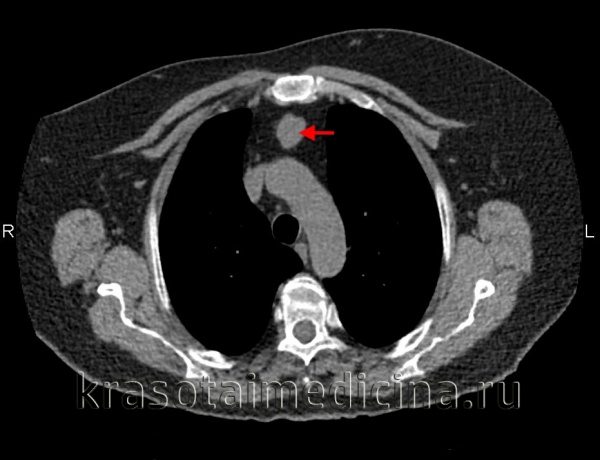

КТ ОГК. Массивное объемное образование верхнего средостения с объемным воздействием на трахею, исходящее из щитовидной железы.